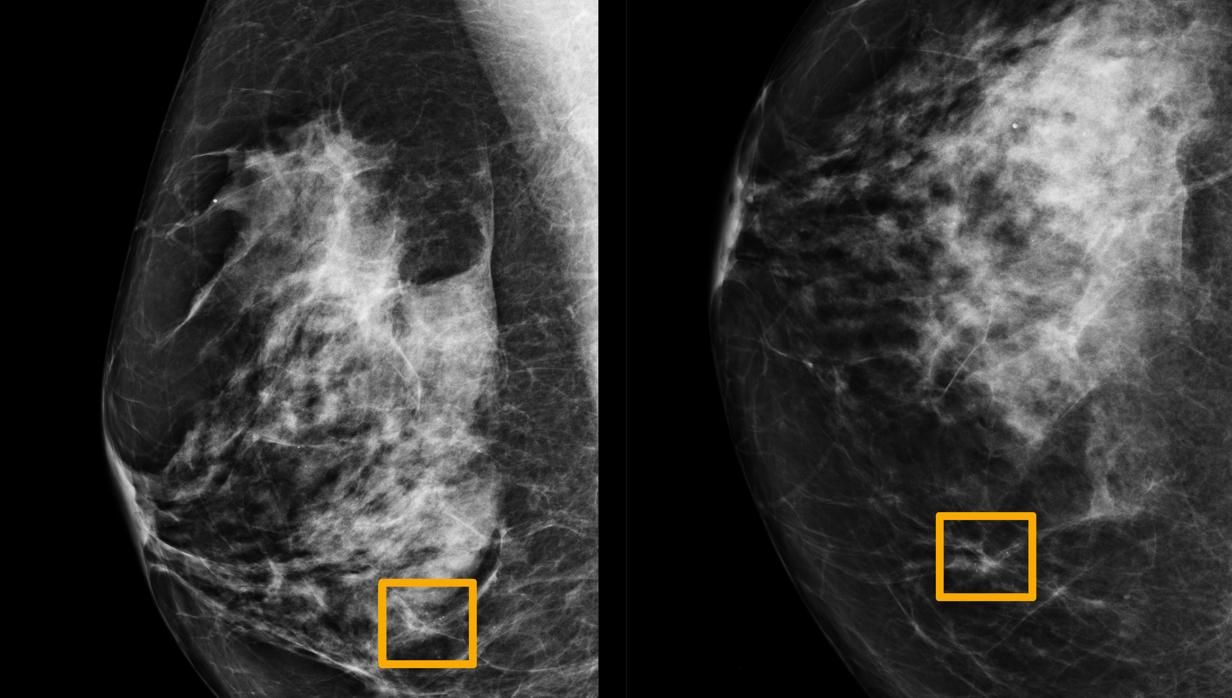

Un cuadro amarillo indica dónde un sistema de IA encontró cáncer escondido dentro del tejido mamario. Seis radiólogos anteriores no pudieron encontrar el cáncer en las mamografías de rutina. Universidad Northwestern

Para evaluar la efectividad de este sistema, los investigadores llevaron a cabo una prueba independiente en la que se compararon los resultados del sistema de IA con los de seis radiólogos. El test de Google superó a todos ellos en la detección precisa de cánceres de mama.